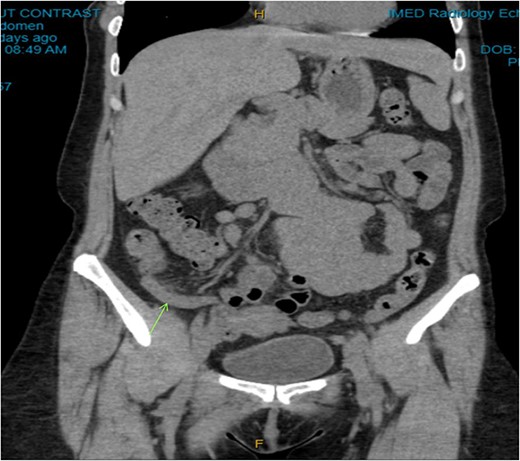

On examination, the patient was alert, but was grimacing in pain. Her abdomen was soft but extremely tender on the right iliac fossa (RIF) region with positive Rovsing’s sign, and rebound tenderness was noted. Vitals were stable. The white cell count was 16.8 × 109/L with left neutrophil shift. The CRP was 102 mg/L. Other laboratory investigations were unremarkable. A computed tomography (CT) scan of the abdomen showed a thickened appendix with adjacent fat stranding which was consistent with acute appendicitis (Figs 1 and 2). Intravenous Augmentin was given pre-operatively and laparoscopic appendectomy was performed on the same day. The patient recovered uneventfully and was discharged the next day. The histological reports revealed appendiceal diverticulitis with transmural mixed inflammation extending out into subserosa and serosa (Fig. 3).

Coronal CT image. Dilated appendix with mild surrounding fat stranding.